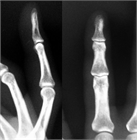

1. 指が物にぶつかって受傷するいわゆる「突き指」には、骨折や靭帯損傷など重度の損傷が隠れている場合がある。

1. 注意深い診察とX線写真撮影により、損傷に応じた適切な治療を行うことが推奨される。